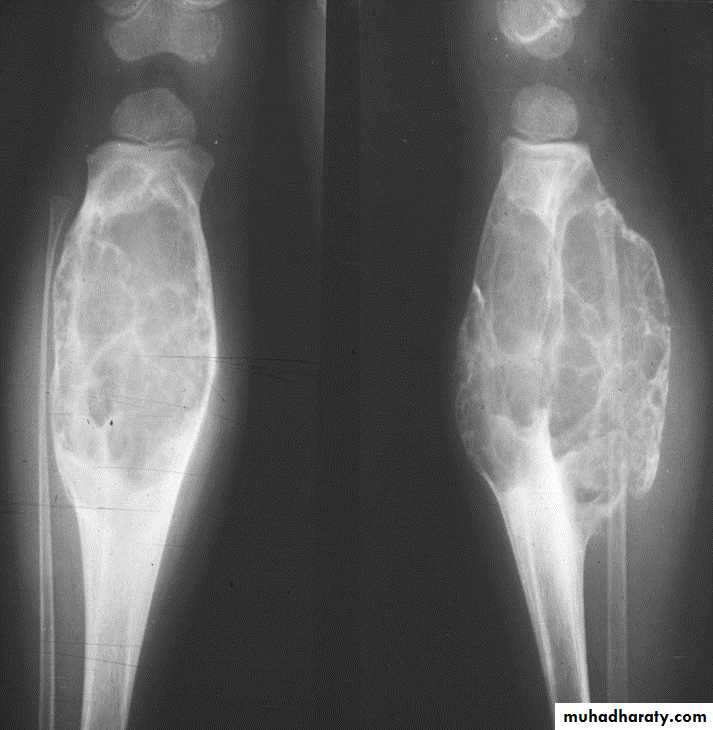

Osteochondroma of the distal femur.

The cortex is continuous with that of the underlying bone and trabecular bone merges with that of the femur. A well-defined cartilage cap contains calcification and is directedaway from the joint.